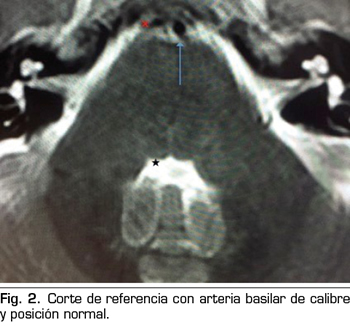

Presentamos el caso de un varón de 59 años, que cursa con un cuadro de parálisis del VI par craneal derecho, tras una cefalea postpunción dural, secundaria a una punción dural accidental durante una epidural. En la resonancia magnética, aparece un compromiso del espacio de la arteria basilar sobre la emergencia del VI par derecho. Posiblemente, esta variante anatómica vascular, lo haya predispuesto a una mayor vulnerabilidad del nervio abducens. La tracción del nervio, pudo producir una isquemia, convirtiendo a la hipotensión licuoral en el posible desencadenante de la parálisis. Con tratamiento conservador se recuperó completamente.

We present the case of a 59 years old man, who is diagnosed with a right sixth cranial nerve palsy, after the development of a dural post-puncture headache, secondary to an accidental dural puncture during an epidural. In magnetic resonance imaging, a compromise of the basilar artery space appears on the emergence of the right sixth cranial nerve. Possibly, this vascular anatomical variant, predisposed him to a greater vulnerability of the abducens nerve. The traction of the nerve could cause a neural ischemia, so intracranial hypotension could be the trigger of the palsy. He recovered completely with conservative treatment.

Figura 2